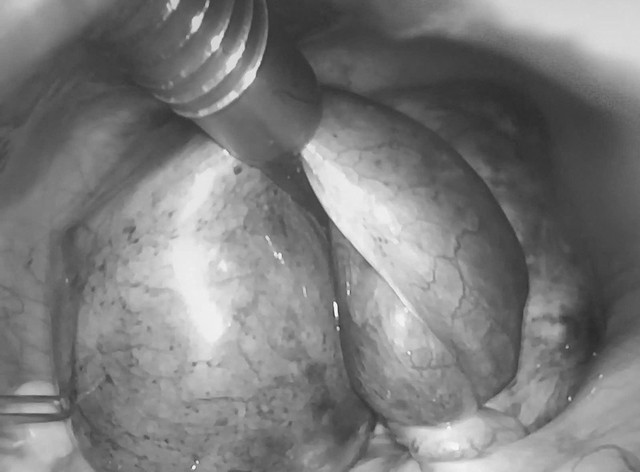

Hình ảnh khối xoắn cơ quan sinh dục gồm buồng trứng, vòi trứng, nang cạnh vòi trứng qua nội soi ổ bụng ở bệnh nhân nữ. Ảnh: Bệnh viện cung cấp.

Trường hợp đầu tiên là bệnh nhân nữ 24 tuổi, chưa lập gia đình, nhập viện trong tình trạng đau hố chậu phải dữ dội, kèm buồn nôn. Qua khám lâm sàng và siêu âm ổ bụng - phần phụ, bác sĩ phát hiện xoắn phần phụ phải, bao gồm nang nước cạnh vòi trứng, vòi trứng và buồng trứng phải.

Bệnh nhân được mổ nội soi cấp cứu tháo xoắn, bóc nang, bảo tồn toàn bộ vòi trứng và buồng trứng phải. Sau mổ, bệnh nhân hồi phục ổn định.

Hình ảnh khối xoắn gồm buồng trứng, vòi trứng, nang cạnh vòi trứng qua nội soi ổ bụng.